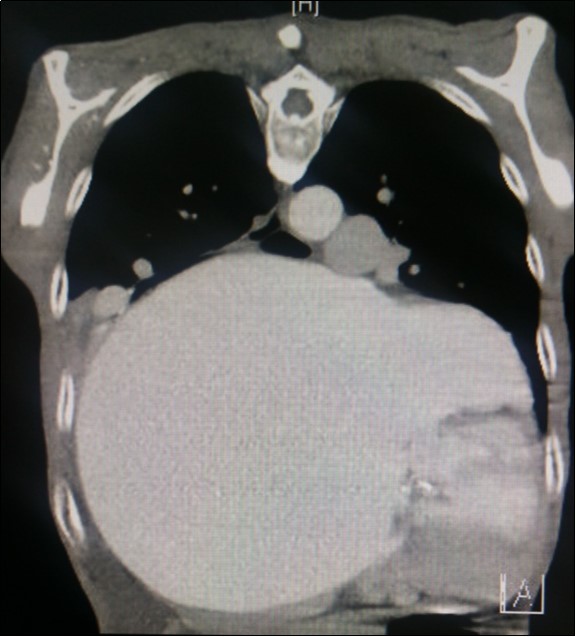

A dramatically dilated left atrium was seen on a TTE (see Figure 2a, Figure 2b, Figure 2c, and Figure 2d). Severe mitral stenosis with associated regurgitation was evident, with a mean gradient across the valve of 11mmHg and a hyperdynamic left ventricle. The left atrial volume measured by Simpson’s biplane method (see Figure 2c) was 2108mL, or 1548.5 ml/m2, based on height 1.55 metres and weight 44 Kg. Normal left atrial volume in a woman is 16 - 34 ml/m21. The computed tomography scan (CT) chest AP view (see Figure 3) is also shown.

Figure 3.Computed tomography scan (CT) chest AP view, showing the extent of the left atrium filling the left and right hemithoraces.

Massive left atrial dilatation is a recognized phenomenon in chronic mitral stenosis, and is considered by some to be protective against the development of pulmonary oedema in mitral regurgitation 2. Left atrial dilatation to this extent is not usually seen in living patients, however. The largest described left atrium was 3000 ml at autopsy, with another measuring 1760 ml at autopsy in 19313. Other reports in living patients include a left atrium that was estimated at approximately 2000ml on magnetic resonance imaging 4.The more precise measurements for the left atrial size we recorded on cardiac ultrasound have not been described previously. Considering the size of the left atrium, it is surprising that the mean gradient across the mitral valve was only 11mmHg. Although this is certainly severe, it could be expected that a gradient would be higher based on the severity of the left atrial dilation. We hypothesize that the gradient may have been greater previously, however the massive dilation of the left atrium may have subsequently led to a dilation of the mitral annulus, leading to an improvement in the mitral valve effective orifice area, and hence a reduction in the severity of the mean mitral valve gradient.